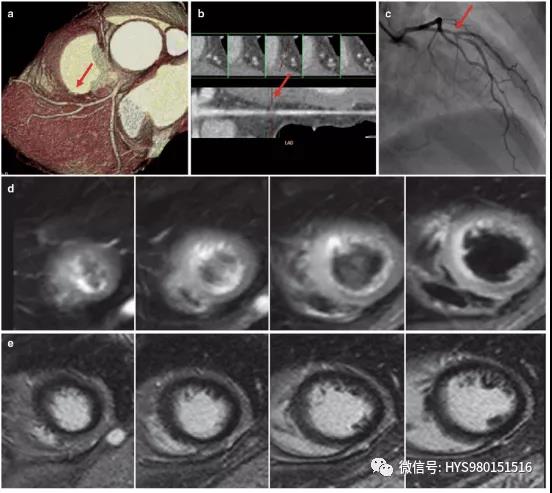

图11 终止心肌梗死。

冠状动脉CT血管造影术(a,b)和常规血管造影术(c)均显示左前降支中段可见重度狭窄(箭头)。

在经皮冠状动脉介入治疗后(c),闭塞的左前降支重新开放。

然而,LGE图像没有显示明显增强(e)。

T2WI图像仅显示心尖部间隔壁、中部前壁和中部近前壁间隔壁(d)的轻微高信号。